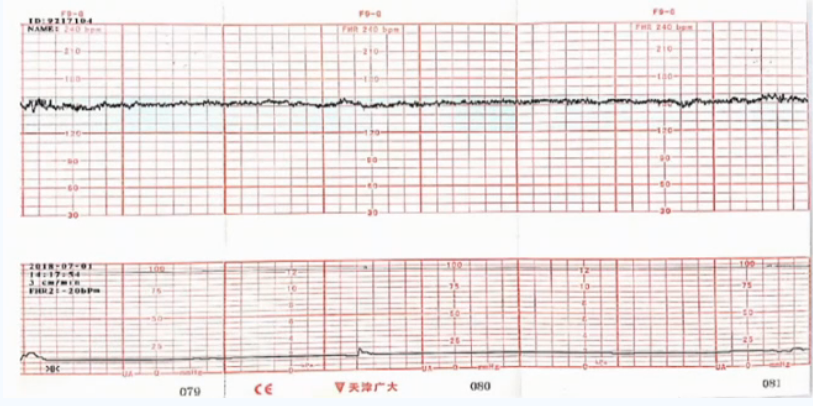

穿戴式胎心监护是基于电生理技术原理设计的外监护设备,弥补了多普勒探头和宫腔压力探头操作复杂、笨重和易受体位干扰的不足。通过贴附于孕妇腹部的穿戴式监测传感器,动态捕获母胎心电信号和子宫肌电信号,经计算机实时处理后描记形成胎心监护图形。这种技术可以避免胎儿心率和母体心率的混淆,有效解决胎心率断线、加倍、减半的问题,适合高危妊娠和胎心监护图形异常孕妇进行长时间连续监护[1]。

穿戴式胎心监护

此外,穿戴式胎心监护设备无外接线束缚,能够实现远程实时胎心监护,操作简单便捷,降低不规范操作带来的干扰。一体化设计不限制孕妇体位及活动,贴片式传感器单次使用可避免交叉感染,便于居家应用,更有利于在疫情防控态势下实施胎儿监护。

由于多普勒胎心率探头可能受到母体腹主动脉搏动信号的干扰,为了避免设备将母体心率误读为胎儿心率,可考虑采用如下方案[3]:①同步监测母体心率,并绘制母体心率曲线;②采用穿戴式一体化胎心监护设备,尤其是肥胖或腹壁过度松弛的孕妇,基于心电信号技术的胎心监护设备可以提高监护效率,无需反复调整探头位置[6-8]。

穿戴式一体化胎心监护